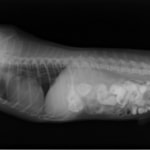

主訴:2日前の夜に桃の種を飲み込んだとのこと。元気・食欲に問題はなく、嘔吐などの消化器症状もみられなかった。誤飲した当日に他院にて催吐処置を試みたが、吐き戻さなかったとのこと。

単純レントゲン検査:明らかな異常所見なし

消化管バリウム造影レントゲン検査:胃内にて異物の存在を疑う異常所見を認めた。

造影直後

内視鏡検査:内視鏡下にて、バスケット鉗子を用いて胃内異物を摘出。

異物内容:桃の種 (約4cm大 写真上)、とうもろこしの芯 (約2.5cm大 写真下)

本症例は、床に落としてしまった桃の種を誤飲していました。動物の体格に対して異物が非常に大きく、開腹手術となる可能性があった症例でした。また、桃の種と一緒に出てきたとうもろこしの芯は、日々のおやつとして与えていたものということでした。とうもろこしの芯は非常に硬く、小さく切って与えても消化されず、長期間胃内に残ってしまうことや腸閉塞の原因となる為、注意が必要です。